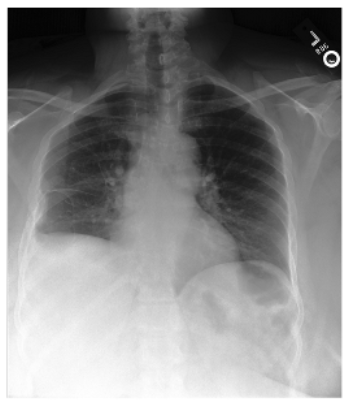

DatasetX-RayGenerated ReportGround Truth

MIMIC-CXRApplsci 16 00470 i003The lungs are clear of focal consolidation, pleural effusion or pneumothorax. The heart size is normal. The mediastinal contours are normal.The cardiac, mediastinal and hilar contours are normal. Pulmonary vasculature is normal. Lungs are clear. No pleural effusion or pneumothorax is present.